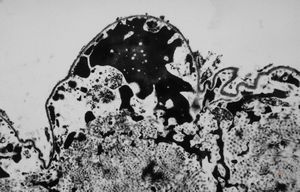

F,49y. | purulent meningitis- meningococcal v.s.

F,49y. | purulent meningitis- meningococcal v.s.

F,49y. | purulent meningitis- meningococcal v.s.